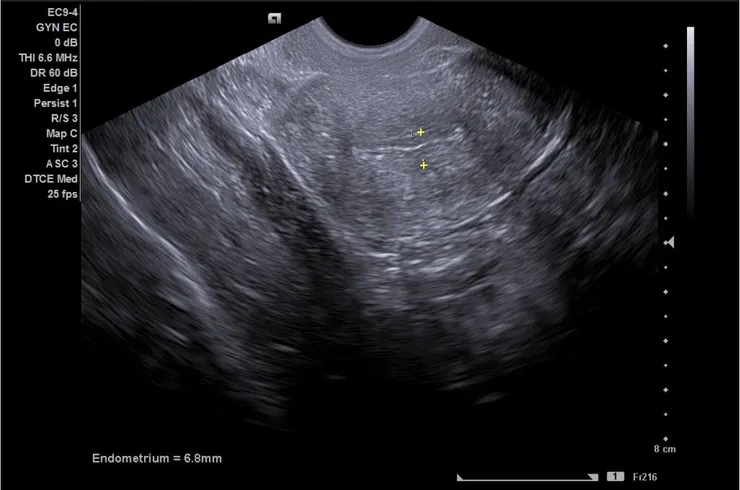

回台灣後驗孕,驗血結果hCG<2.3,我們像洩了氣的皮球開始找原因,網路上面醫生說內膜植入最佳厚度是0.8-1.2cm,我們看了美國給的轉黃體前超音波照片上面顯示「6.8mm」,開始懷疑是不是內膜長的不夠好?可能劑量太低或者是身體對藥物反應不佳。

D15回診內膜6.8mm,E2=265.9/P4=0.39